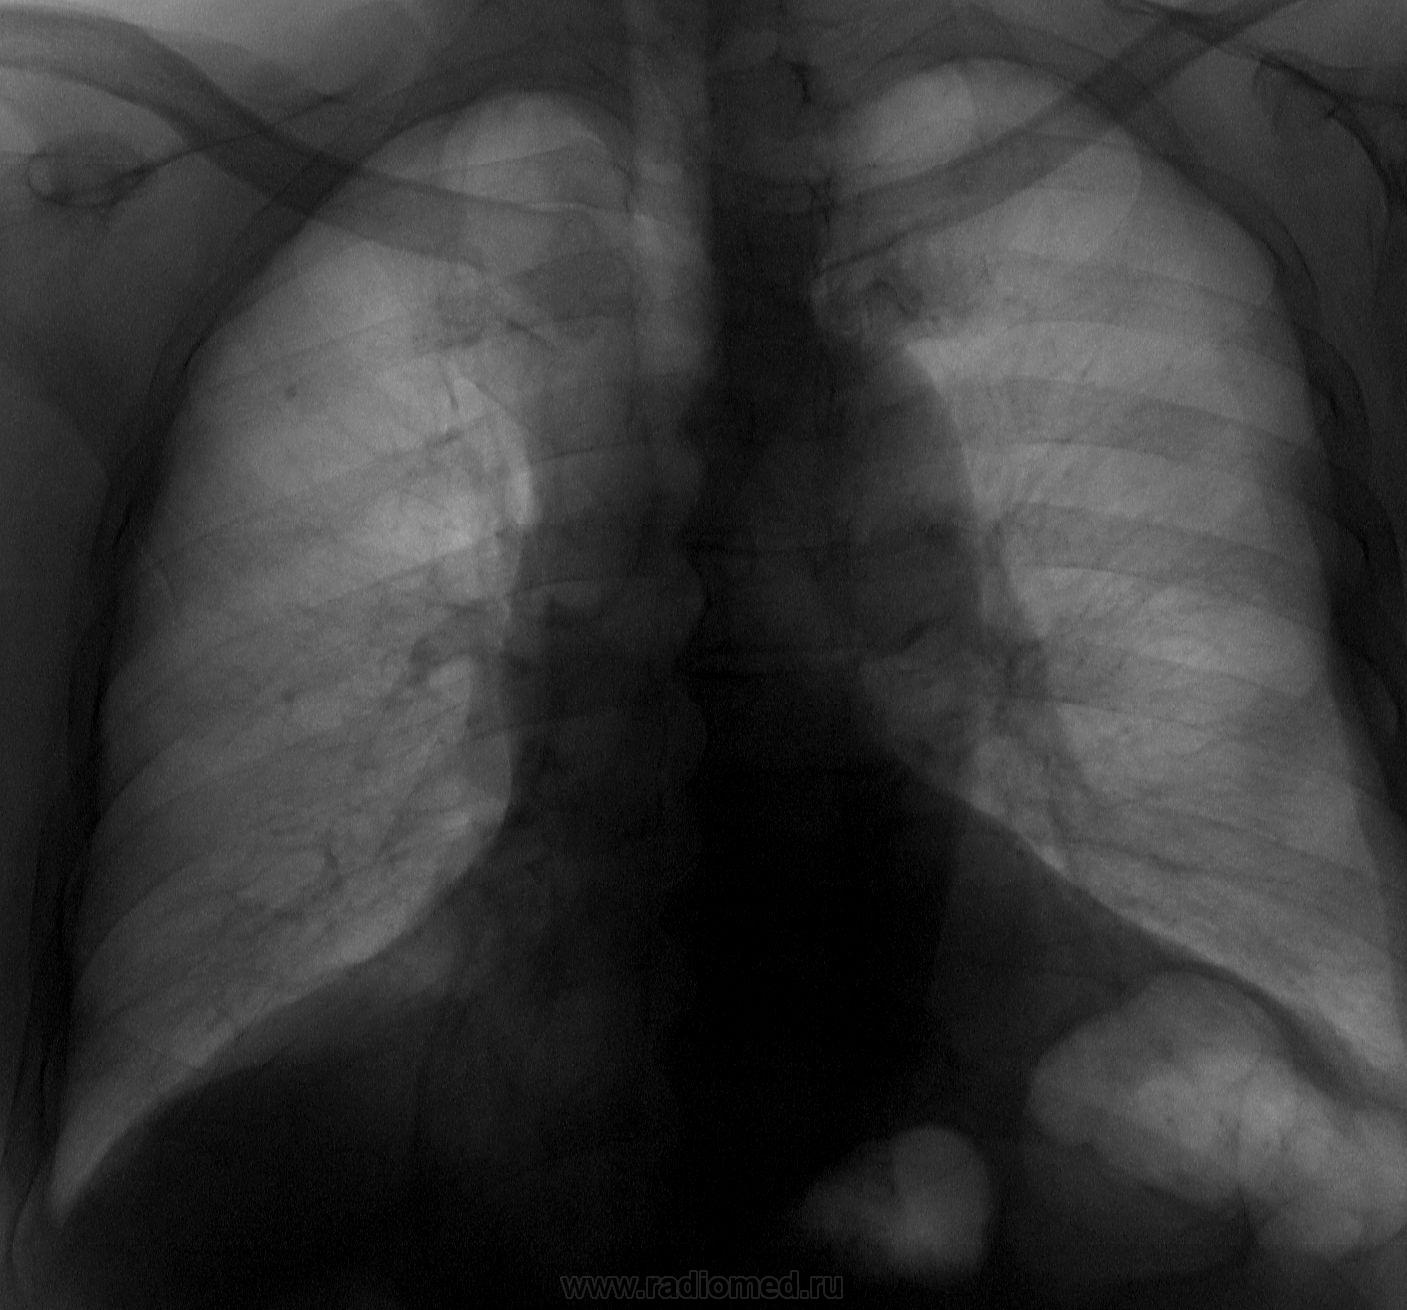

Идеальных легких не так много, вот и приходится из "неидеала" выбирать "норму", или "около нормы" ( типа. жил человек до этого, и дальше потянет). При большом потоке флгр. таких каждый день довольно много, если всех на контроль - не разгребешь. Тем более, если флюорограф не на основном месте работы, а ближайший кабинет через 7 этажей, и томограф не работает, а всего 0,5 ст...Ну вот такой дед, как сегодня - пришел на проф. флгр. Он набрал всячины за свою тяжелую социалистическую жизнь, или там справа нижняя доля спалась?

Какая-то диафрагма странная... По мне так пусть живет...

Да судя по междолевой с нижней долей нето.., на дообследование дедулю, хотя и подворот, но левое легочное поле больше и межреберные слева шире..

Так эта странная диафрагма и смущала (на подобии с-ма кулис). Иногда так доля ателектазирует, что и не заметишь, что ее нет. Хорошо, что есть архив. Хотя в первый раз особых подозрений у меня не возникло (судя по моему описанию). А все-таки динамика (или ее отсутствие) это помогает.

Аталектаз может и есть, но видно очень старый.. как исам дедуля...)

Коллеги - а если ...."... диафрагма опущена, имеет форму палатки".....Как вам такой расклад?...ведь диафрагма с двух сторон такая....так что пусть он живет дальше, единственное - поинтересоваться анамнезом ...ну там хронический бронхит....или еще какое чудо...

При раздумьях делаю боковой, что по сто раз на одну и ту же тему думать, раздумья дороже стОят